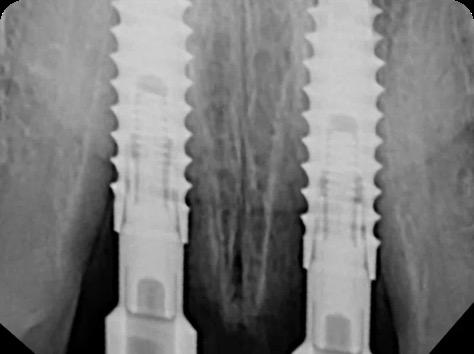

BioHorizons has introduced a new implant system that combines the advanced thread design of the Tapered Pro with the precision and stability of the Conelog conical connection. This integration delivers enhanced surgical handling, improved primary stability, and long-term biological benefits, supporting better patient outcomes in both aesthetic and functional zones.

This case was performed by Dr Homa Zadeh, DDS, PhD, a respected leader in periodontology and implant dentistry. Dr Zadeh’s approach emphasizes biologically driven protocols and evidence-based techniques, making this case a strong example of clinical excellence using the Tapered Pro Conical system. It involves the replacement of two front anterior teeth after they fractured off and the full restoration process.

Fig 2. Intraoral radiograph indicating tooth structural loss extent.

Fig 6. BioHorizons Tapered Pro Conical implants of 3.8 x 15mm placed according to the plan.

Fig 9. Periapical radiograph for verification of proper seating of the scanbodies.

Fig 13. Radiograph of implants, grafts and Provisionals.